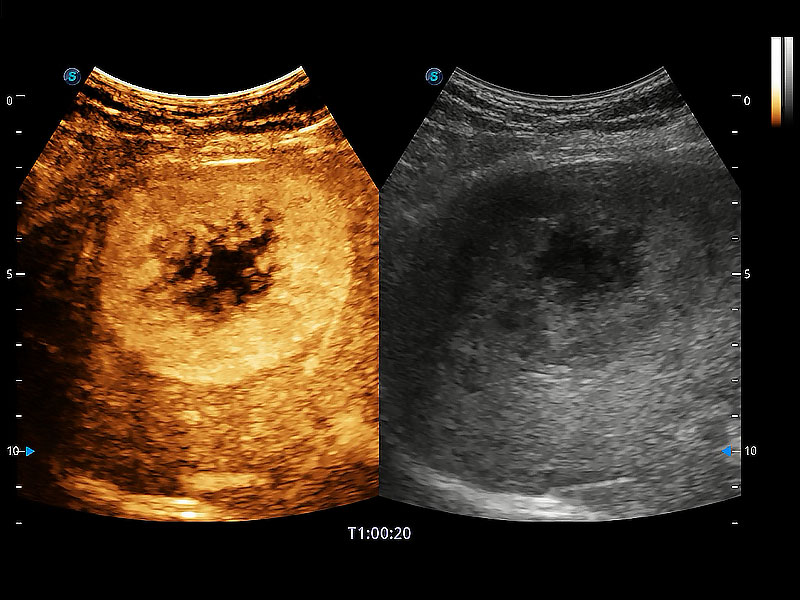

高性能和先进的临床应用工具可以为动物医生提供临床信心。ProPet 80 搭载了先进的腹部和浅表应用工具,帮助医生在日常临床实践中发挥前所未有的作用。

极大提升超低速微细血流的检出能力,同时更精准地滤除软组织和超声信号,为兽用医生提供以往无法通过常规血流获得的疾病诊断信息。

操作简便,无需高频度外力作用即可真实反映组织的形变,快速评估肿瘤良恶性。

非线性融合造影成像充分利用谐波和基波信号,为难以观察的血流进行增强显像。可用于线阵、凸阵、微凸阵、相控阵探头。